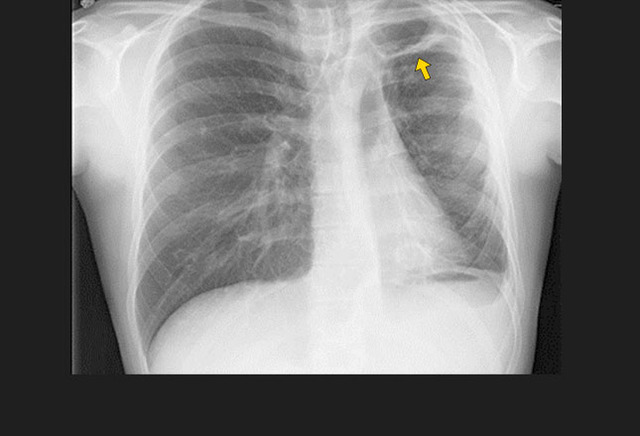

图1. 一位进展性肺结核患者双侧胸腔积液(左侧较右侧严重)。

影像学特征包括斑片状或肺叶的实变、空洞(继发性肺结核的典型表现)、纵隔淋巴结肿大和胸腔积液。继发性肺结核常侵犯上叶尖后段及下叶背段。代表着血行播散的粟粒型肺结核并不常见,但预后不佳。